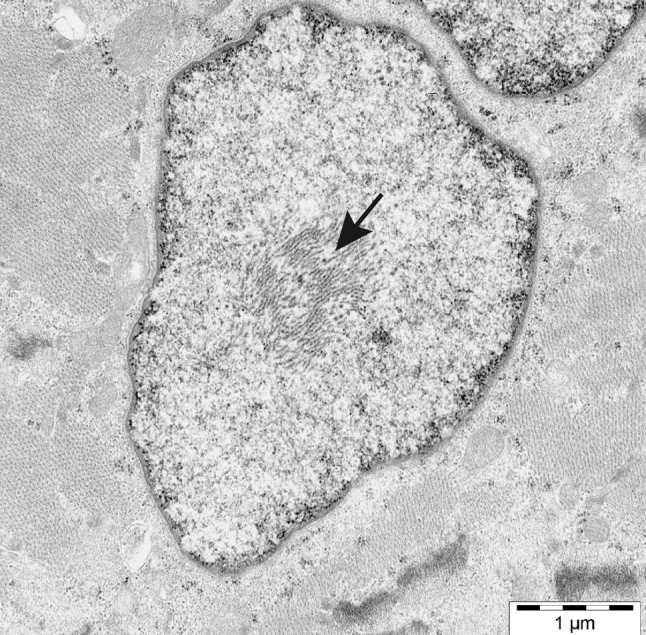

Fig. 7.

Electron micrograph illustrating intranuclear filaments (arrow) in dominant myosin IIa myopathy